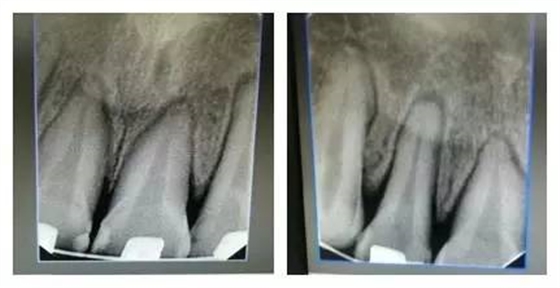

每一位臨床醫(yī)生每天都會面臨各種困惑和難題,只要我們堅持思考,善于溝通、勤于實踐,(牙合)學(xué)的神秘大門將會為我們敞開。這是權(quán)老師最初在(牙合)學(xué)群里分享的一句話。最近,權(quán)老師在(牙合)學(xué)群里分享自己的病例,“堅持思考,善于溝通、勤于實踐”,她不僅用這樣的話激勵群里的每一位同仁,更一直在行動著。讀讀病例,讓我們開始思考…… 病例:患者,女,22歲。 主訴:8年前曾行正畸矯正,現(xiàn)因美觀及功能需求,要求重新矯治。 現(xiàn)病史:2個月前,開始戴用矯治器,以0.012Niti初始絲,近2個月來無明顯不適。2天前,上前牙開始出現(xiàn)咬硬物疼痛,冷熱刺激痛,自覺松動。 檢查:上前牙松(Ⅱ)°,牙齦紅腫,牙周膜間隙增寬。(如照片所示)

口內(nèi)情況,如以下照片所示: